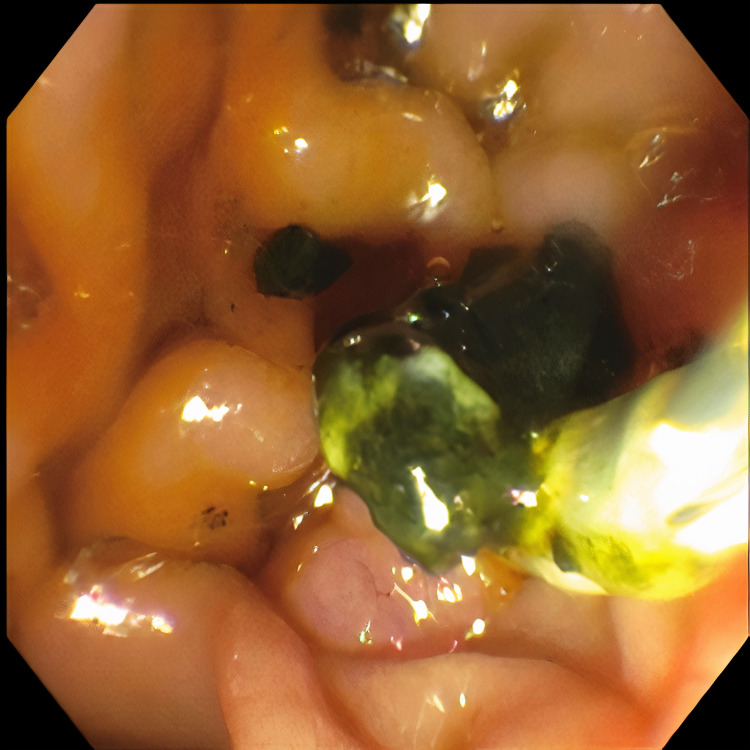

Pertinent labs include elevated white blood cells (13.5×10³/µL), total bilirubin (15.7 mg/dL), direct bilirubin (11.7 mg/dL), aspartate aminotransferase (98 U/L), and alanine aminotransferase (41 U/L). Urinalysis showed tea-colored urine. CT scan of the abdomen and pelvis revealed a collapsed gallbladder with CBD obstruction and bile duct dilation consistent with chronic inflammation. Endoscopic retrograde cholangiopancreatography (ERCP) was then performed which demonstrated cystic duct stone eroding into the common hepatic duct, hence the diagnosis of Mirizzi syndrome was made. Cholangioscopy confirmed the eroding stone, chronic inflammatory changes, and destruction of the bile duct. A cholecystoduodenal fistula with pus drainage was noted in the duodenal bulb. The patient was diagnosed with MS type V according to the ERCP findings. The stone was not amenable to endoscopic removal, but stone debris, clots, and pus (Figures 1–4) were swept. He was referred to the surgical team for cholecystectomy and repair of cholecystoduodenal fistula.